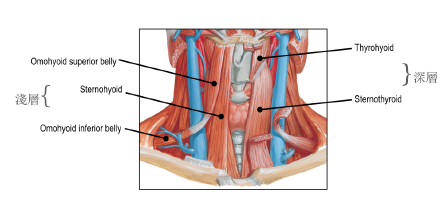

舌骨下

| 肌肉 | 神經支配 |

|---|---|

| Omohyoid | Ansa cervicalis |

| Sternohyoid | |

| Sternothyroid | |

| Thyrohyoid m. | C1 |